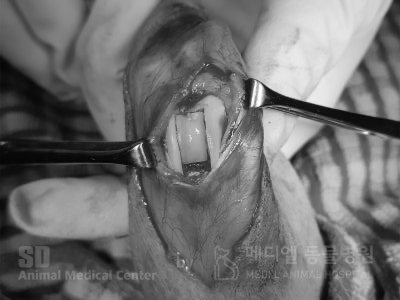

슬개골탈구 수술 사진입니다. 이번 수술에는 지대중첩과 경골조면이식술(TTT)로 진행되었습니다.

이 환자의 경우에는, 슬개골이 꽤 진행되어있어서, 활차구성형술과 함께 경골조면을 이동시켜주는 방법까지 추가되었습니다.

활차구 성형술(TBR : Trochlear Block Recession)

슬개골이 위치하게되는 활차구의 홈을 더 깊게 성형하는 방법

경골조면이식술(TTT : Tibial Tuberosity Transpositon)

돌아간 경골 조면부분을 절골해 회전시켜 슬개골의 위치를 제자리로 만들어 주는 방법